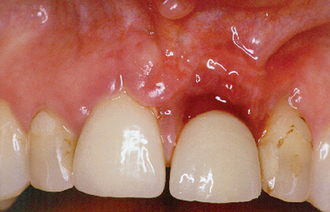

Patients should be informed of pain, swelling and bruising of the face arising after surgery. Damage to adjacent teeth may occur through carelessness or difficulty in locating the apex of the tooth to be treated. This latter complication should be anticipated preoperatively. Contraction of the mucoperiosteal flap may occur through scarring as it heals, leading to unsightly recession around the gingival margin (Fig. 6.5). A judicious approach to flap design, reflection, retraction and careful suturing of the flap after surgery should avoid this problem.

Fig. 6.5 Loss of tissue at the gingival margin of the upper left central incisor following surgical endodontics.